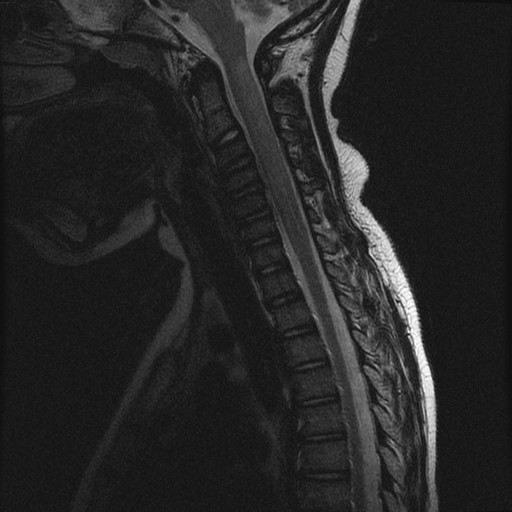

Durante il ricovero è stata eseguita RM di encefalo e midollo con mezzo di contrasto, che confermava la presenza di aree di alterato segnale già note a livello sovra- e sotto-tentoriale e il coinvolgimento midollare a livello di C1-C2, C4-C5, D10-D11 queste ultime con enhancement al contrasto, alterazioni compatibili con lesioni demielinizzanti ad andamento recidivante-remittente in fase attiva (Figure 1-3).